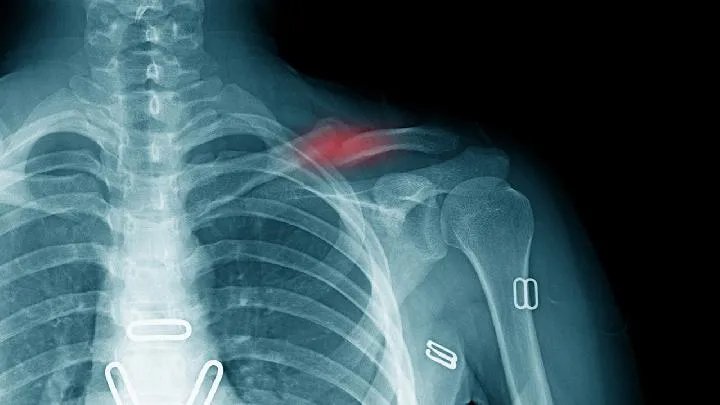

1、X线检查:

a.疑似锁骨骨折时需摄X确定线像诊断。

一般来说,1/3锁骨骨折的前后位置和向头倾斜45°斜位相。

拍摄范围应包括锁骨全长、肱骨1/3、肩胛带和上肺野。必要时,另行拍摄胸片。

前后位相可显示锁骨骨折的上下移位,45°斜位可观察骨折的前后移位。

d.锁骨前后位1/3X线像与纵隔和椎体重叠,不易显示骨折。向头倾斜40°~45°X有助于发现骨折线。

X虽然常用线检查,但误诊率高,检查时不能满足X线正位片未见骨折,诊断为软组织损伤,应仔细检查是否有锁骨内端或局部骨折,以便正确诊断。